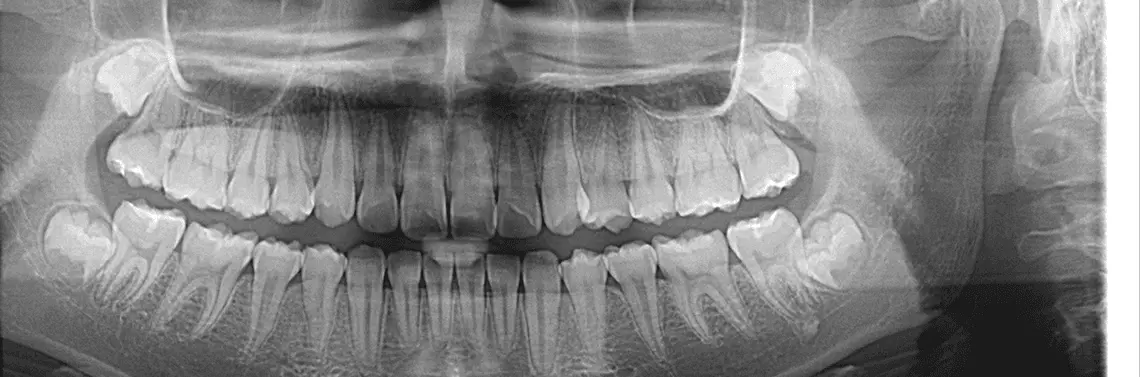

Równocześnie klasyczna diagnostyka endodontyczna nie jest wystarczająca dla rzetelnej oceny stanu faktycznego. Nie zawsze stomatolog jest w stanie dokładnie odpowiedzieć na pytania, jaką techniką wykonać leczenie, kiedy je wykonać, jak uniknąć powikłań, jakie są zagrożenia i jak zminimalizować ryzyko. Dlatego też współcześnie, chcąc zapewnić najwyższy standard leczenia, endodontyczny protokół diagnostyczny warto wzbogacić o diagnostykę 3D (zdj. 1). Z wywiadu można dowiedzieć się o skargach i oczekiwaniach pacjenta, zaś badaniem klinicznym ocenia się wartość strategiczną zęba, możliwość odbudowy, badaniem rentgenograficznym (RTG)/radiowizjograficznym (RVG) można ogólnie ocenić problem pacjenta, natomiast diagnostyka CBCT (ang. cone beam computed tomography)/3D w dużo większym zakresie pozwala na szczegółową analizę problemów endodontycznych.

Spośród wielu informacji, które dostępne są podczas analizy obrazu 3D, kilka wybija się na pierwszy plan, w zasadniczy sposób pomagając w trudnym procesie podejmowania decyzji.

1. Dokładna morfologia:

- ocena przebiegu poszczególnych kanałów – program komputerowy pozwala na uzyskanie przekroju w dowolnej płaszczyźnie, umożliwiając np. zobrazowanie każdego kanału górnego zęba trzonowego osobno, włącznie z kanałem MB2. Trudno przecenić takie informacje, szczególnie że można sprawdzić drożność poszczególnych kanałów, zmierzyć promień krzywizny, ocenić miejsca podziału/połączenia kanałów, sprawdzić obecność kanałów bocznych (zdj. 2a, b, c, d);

- ocena powikłań – podczas leczenia powtórnego doskonale widoczne są m.in. spoistość i zasięg poprzednich materiałów wypełniających, dokładne położenie złamanego instrumentu, obecność perforacji czy też stopni;

- stan wierzchołka – przy odpowiedniej manipulacji obrazem CBCT można zobrazować wierzchołek każdego z korzeni i sprawdzić kierunek i kąt ujścia, szerokość, obecność przewężenia fizjologicznego lub jego brak, resorpcję wierzchołka. W przedstawianym podczas kursu przypadku kanał korzeniowy zęba 25 uchodzi w kierunku podniebiennym i jest zlokalizowany w odległości około 1,5 mm od wierzchołka zęba (zdj. 3),

- pomiary długości kanału korzeniowego – są bardzo precyzyjne i porównywalne z pomiarami elektroendometrycznymi.

2. Ocena tkanek okołowierzchołkowych:

- obecność zmian okołowierzchołkowych – klasyczne zdjęcie RTG/RVG w porównaniu do obrazu CBCT oferuje niską wartość diagnostyczną w kontekście oceny tkanek okołowierzchołkowych. Wieloletnie doświadczenie pokazuje, że codziennością jest niedoszacowanie stanów zapalnych i innych patologii okolicy wierzchołka podczas korzystania wyłącznie z diagnostyki dwuwymiarowej. Charakter klasycznego badania RTG skutkuje nakładaniem się wielu struktur, dając w efekcie obraz, który nierzadko daleki jest od rzeczywistości. Przypadki zaklasyfikowane nawet przez doświadczonych specjalistów endodoncji jako „brak zmian okołowierzchołkowych”, w obrazie CBCT nierzadko zmieniają status na „przewlekły stan zapalny tkanek okołowierzchołkowych” (zdj. 4);